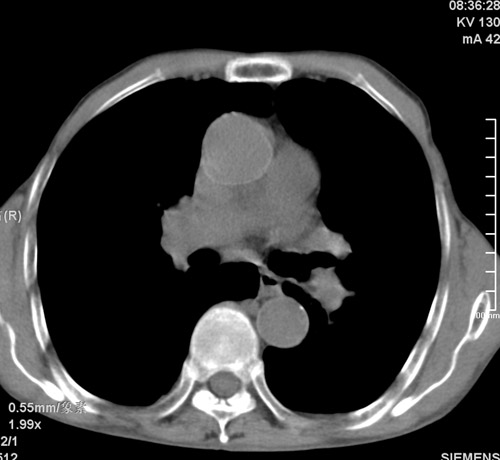

标题: CT17529:男 76 胸背部不适半月 胸透支气管炎 行CT检查 [打印本页]

标题: CT17529:男 76 胸背部不适半月 胸透支气管炎 行CT检查

意见 老年肺 少许炎症 肺大泡 右肺门略大 但支气管通畅  请各位高手指教如何下意见

支持楼主意见,右肺门略大,可能为肺动脉增粗.

慢支肺气肿,肺动脉高压.